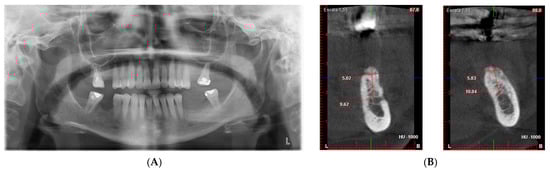

- After 7 and a half months, the Avinent® 3.8 × 8.5 implants were placed in position 3.5 and 4 × 8.5 in position 3.6 (Figure 11). The torque of the implants was greater than 45 N/cm. The ISQ of both implants was taken, being 82 buccal and palatal for the implant in position 3.5 and an ISQ of 57 buccal and palatal for the implant in position 3.6. The bone gain obtained was 1.84 and 1.92 mm in width and 4.2 and 3.78 mm in height for positions 3.5 and 3.6. Simultaneously with the placement of the implants, a bone biopsy was performed between the implants, using a 2 mm bone trephine (Sanhigia, Bujaraloz, Spain) (Figure 12). Three months after the placement of the implants, the implants were rehabilitated using metal-ceramic screw-retained crowns.